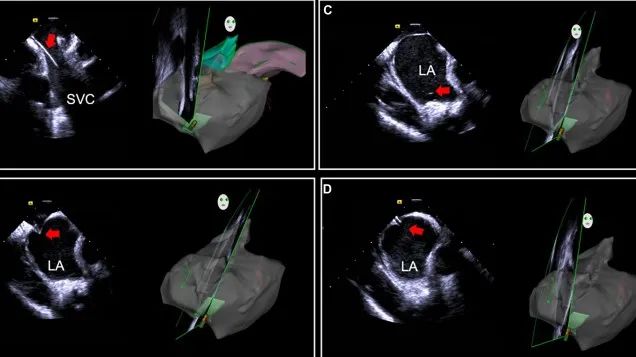

一種與心導(dǎo)管檢查相結(jié)合的超聲心動圖診斷新興技術(shù),通過將超聲探頭置于心腔內(nèi)部,發(fā)射并接收超聲信號,來精確獲取心臟解剖結(jié)構(gòu)、心臟血流動力學(xué)等信息的實時成像。與其他影像技術(shù)相比,ICE技術(shù)具有操作簡單、無輻射、安全性高、手術(shù)效率高、實用等優(yōu)勢,ICE在很大程度上有望取代經(jīng)食道超聲心動圖(TEE),成為電生理和結(jié)構(gòu)性心臟病領(lǐng)域的理想成像方式。

目前ICE技術(shù)已被應(yīng)用于左心耳封堵、房顫射頻消融、二尖瓣成形、房間隔缺損封堵等多種心臟介入手術(shù),應(yīng)用場景主要圍繞臟電生理、結(jié)構(gòu)性心臟病等領(lǐng)域,目前以電生理應(yīng)用為主。數(shù)據(jù)顯示,我國結(jié)構(gòu)性心臟病介入器械市場規(guī)模已從2017年的4億元增長至2021年的20億元,年復(fù)合增長率達48.3%;預(yù)計到2025年,該市場規(guī)模將達到104億元,可以預(yù)見ICE市場規(guī)模也將同步高速增長,未來市場發(fā)展空間廣闊。

心腔內(nèi)超聲(ICE)技術(shù)壁壘極高,國內(nèi)主要廠商核心部件仍舊為進口,集成了超聲和圖像處理最前端技術(shù),包括超聲探頭、線纜、軟件成像算法等,是當前內(nèi)窺超聲方向最具挑戰(zhàn)的領(lǐng)域。ICE的應(yīng)用經(jīng)歷了2D平面成像、3D三維立體成像、以及4D的實時三維立體成像階段。